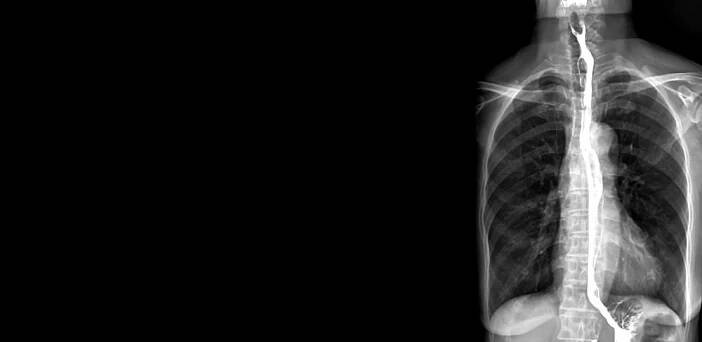

K odhalení rakoviny jícnu slouží fyzikální vyšetření, laboratorní vyšetření krve, rentgen jícnu, endoskopie s biopsií, endosonografie a CT hrudníku. Zdroj: Shutterstock.com